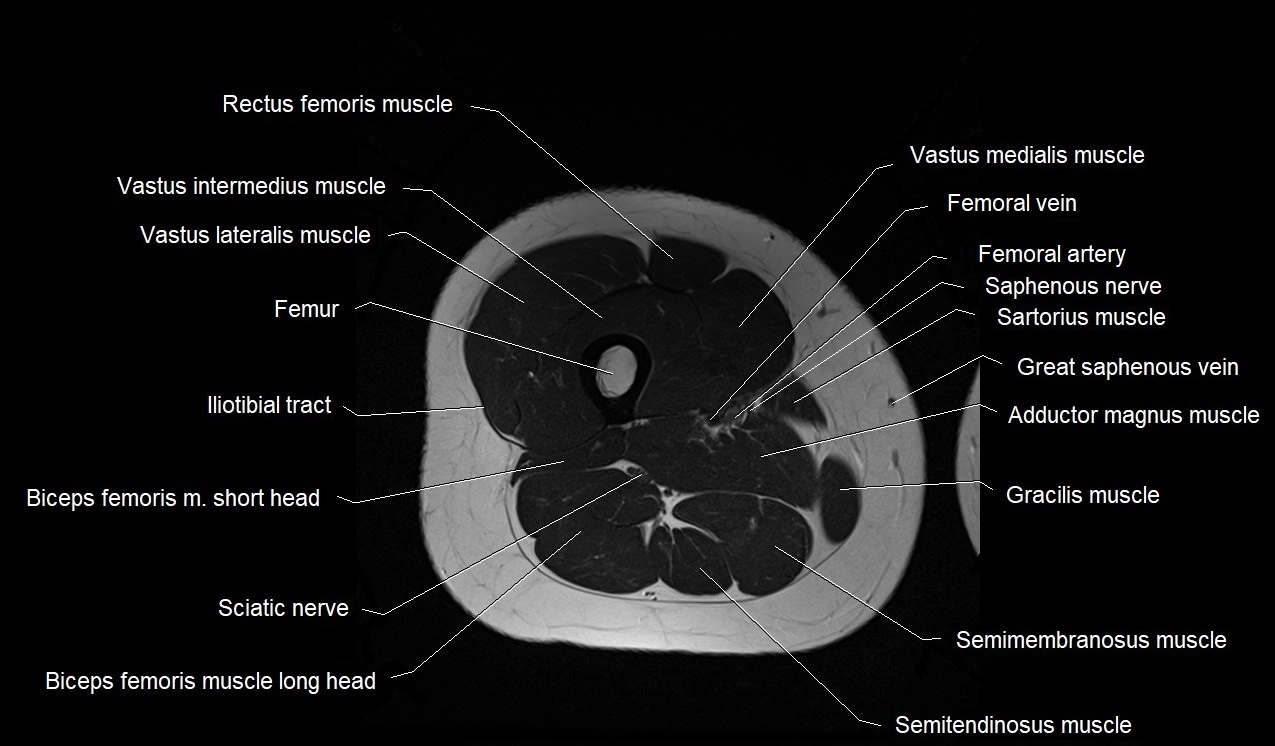

- Femoral artery

- Femoral vein

- Gracilis muscle

- Iliotibial tract

- Rectus femoris muscle

- Saphenous nerve

- Sartorius muscle

- Semimembranosus muscle

- Semitendinosus muscle

- Vastus intermedius muscle

- Vastus lateralis muscle

- Vastus medialis muscle